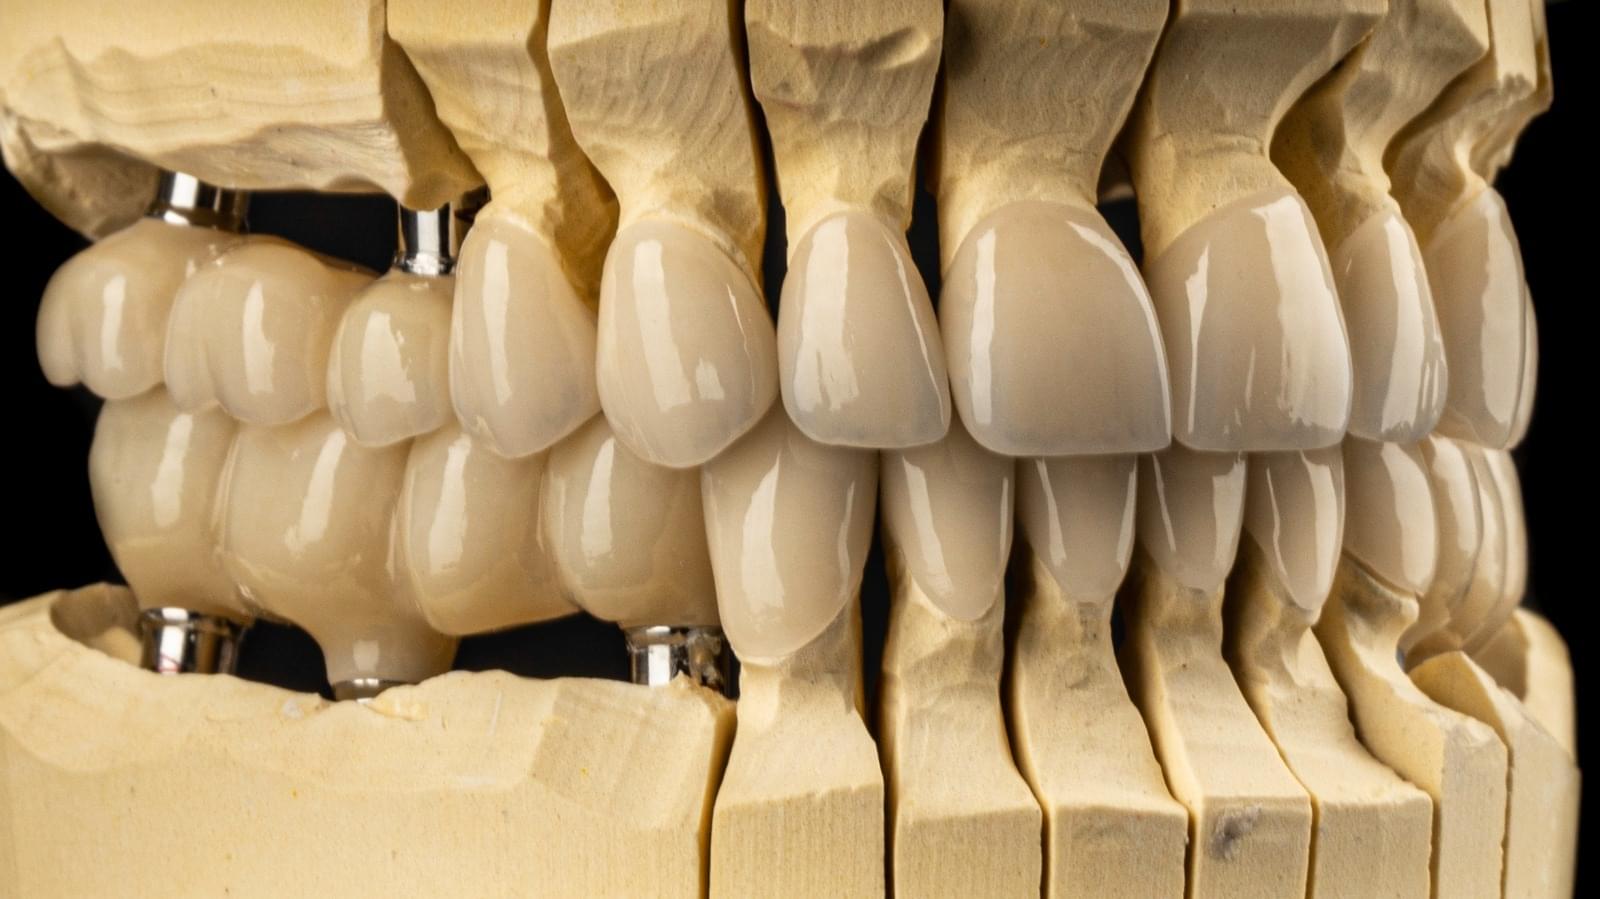

Implanturi Dentare 🔥 Cazuri finisate #1